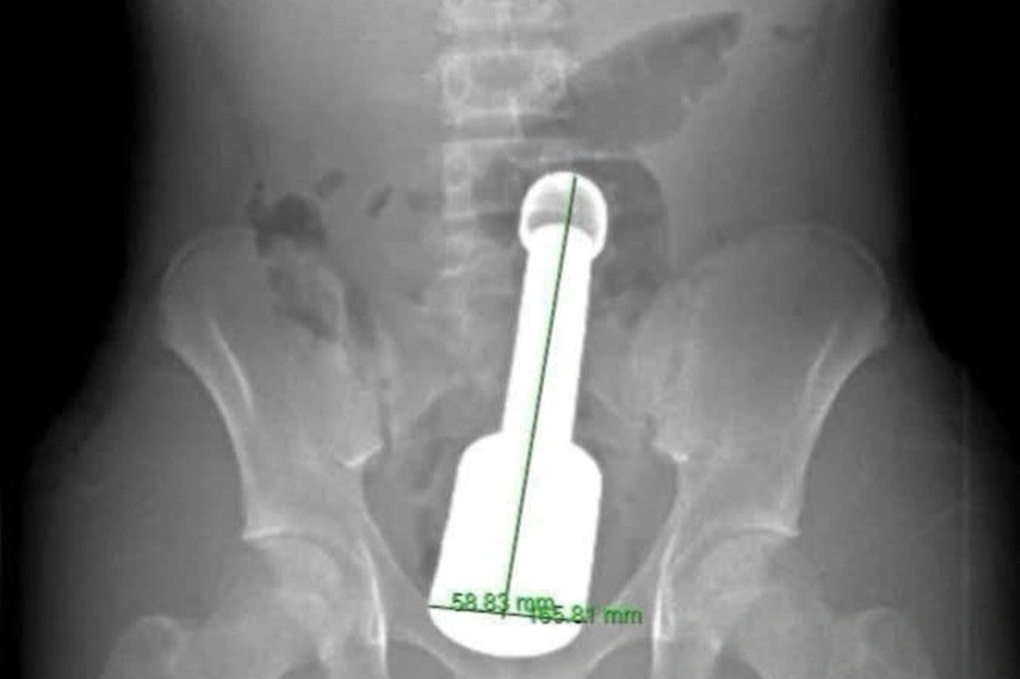

Nam bệnh nhân N.K.N. (15 tuổi, Hà Đông, Hà Nội) được gia đình đưa vào viện cấp cứu trong đêm, với biểu hiện đau tức dữ dội vùng hạ vị. Kết quả chẩn đoán hình ảnh xác định một dị vật kim loại kích thước lớn mắc kẹt sâu trong trực tràng, gây chèn ép các cơ quan vùng chậu.

Hình ảnh dị vật bị kẹt trong trực tràng bệnh nhân (Ảnh: Bệnh viện cung cấp).

Thử thách đặt ra là cực lớn: chiếc chày không chỉ to (đường kính 6cm là giới hạn cực đại đối với cơ thắt hậu môn của một thiếu niên) mà còn rất nặng và tạo ra “hiệu ứng chân không” phía trên đỉnh dị vật. Điều này khiến nó bị hút chặt vào lòng ruột.